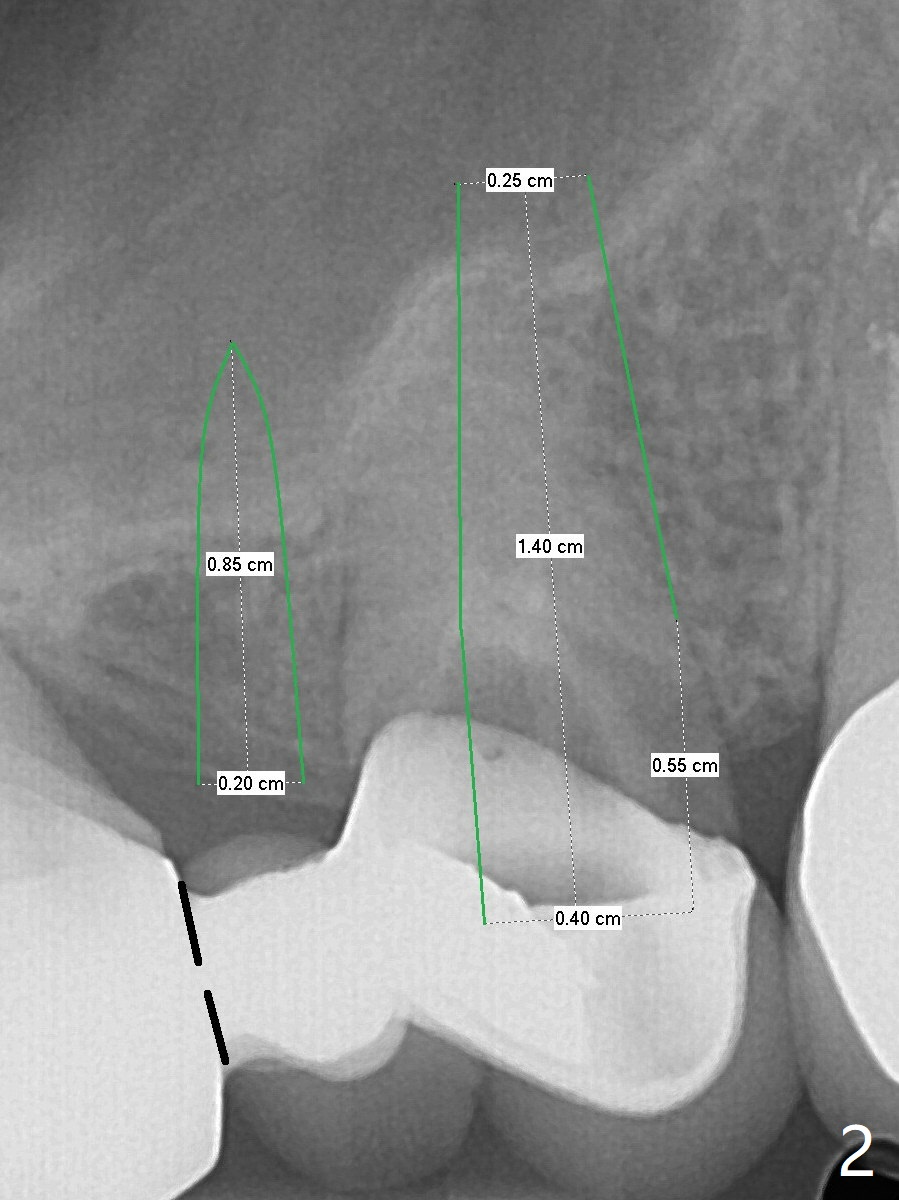

After sectioning the FPD as indicated by black dashed line in Fig.2, try to initiate osteotomy at #3 with 1.2 and 1.5 mm drills for 5 mm (bone height) and 1.0 and 1.5 mm Tatum micro-osteotomes for sinus lift and place a 2x8.5 mm IS mini-implant.  If it is feasible, place a 4x14 mm tissue-level implant slightly mesial at #4.  If not, place a larger one (4.5 mm) slightly distal for a cantilever FPD.